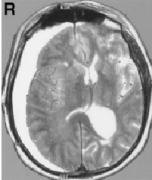

就定义而言,如果脑动脉瘤直径达到或超过25mm就称为较大动脉瘤。这些动脉瘤的根本特性及其解剖复杂性使其成为神经外科医生较难解决的病变之一,而其不容乐观的自然转归又使得需...